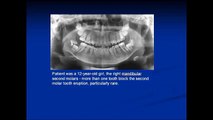

A Rare Case More Than One Tooth Block the Second Molar Tooth Eruption